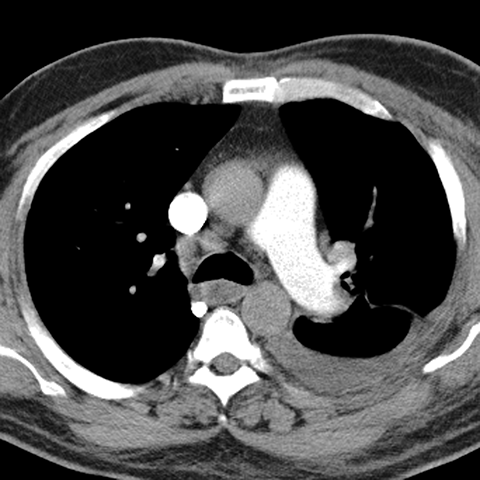

Pleural Effusion, Small to Moderate [4 of 5]